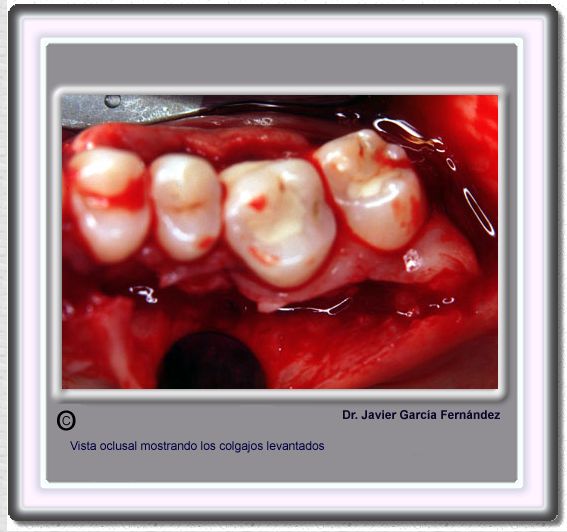

image 212